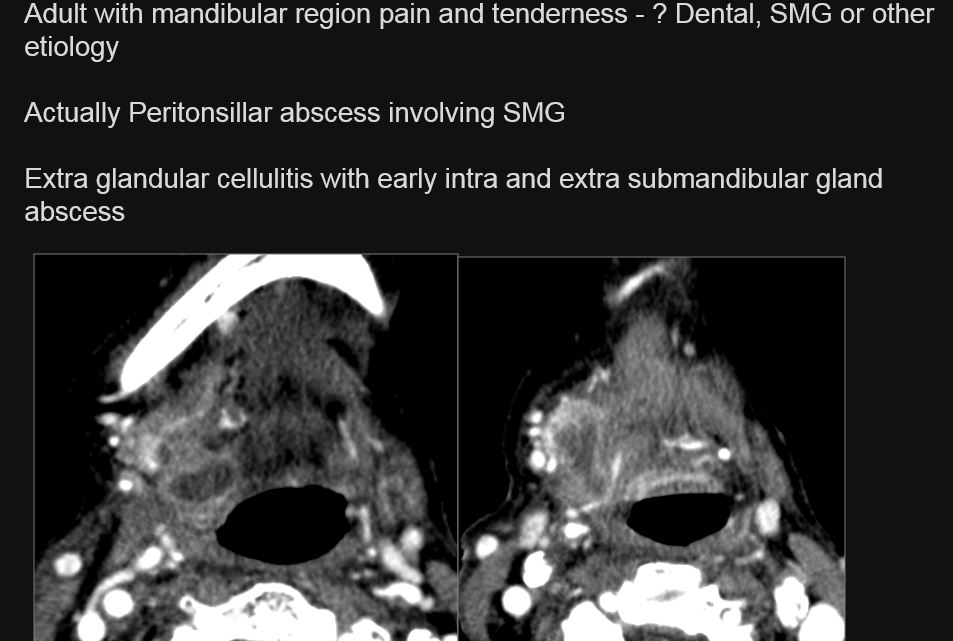

There is a developing abscess within the submandibular gland.

There is edema (cellulitis) and/or abscess within the fat surrounding the submandibular gland and/or of the submandibular, sublingual or other adjacent spaces.